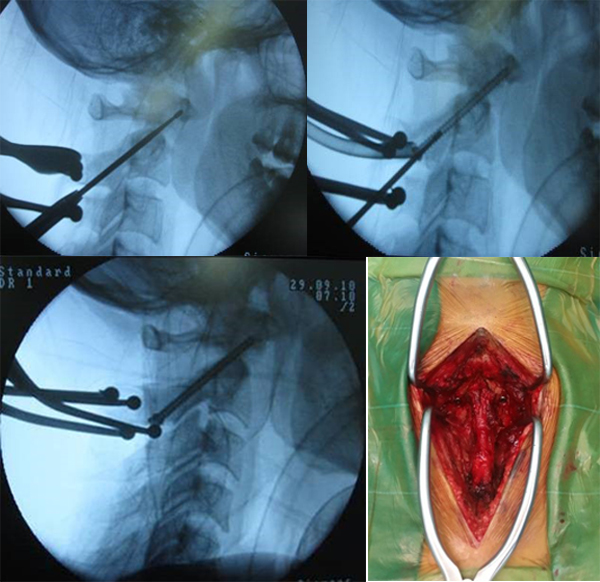

Kỹ thuật vít qua khớp:

– Gây mê nội khí quản

– Tư thế nằm sấp, đầu cố định trên một gá đỡ

– Rạch da đường cổ sau từ ngang lỗ chẩm đến gai sau C7

– Bóc tách theo các lớp bộc lộ diện khớp C2 – C3 và cung sau C1

– Vị trí đặt vít qua cuống C2: Trên diện khớp C2 – C3 khoảng 2 – 3 mm và ra ngoài so với bờ trong diện khớp 2 – 3 mm

– Nắn chỉnh di lệch trên màn tăng sáng sao cho diện khớp C1 – C2 về đúng vị trí giải phẫu.

– Hướng mũi khoan mồi và vít hướng tới cung trước C1 theo chiều trước sau và tạo góc so với mặt phẳng cắt đứng dọc qua đường giữa một góc 0 – 10 độ, hướng về phía củ trước C1.

– Liên tục kiểm tra trên màn tăng sáng trong mổ đề phòng tổn thương động mạch đốt sống hoặc vào trong ống sống gây tổn thương thần kinh.

– Ghép xương liên cung sau C1 – C2

– Đóng vết mổ

– Sau mổ bệnh nhân được cố định cổ bằng nẹp hỗ trợ bên ngoài từ 4- 6 tuần

– Đánh giá lâm sàng và chẩn đoán hình ảnh sau mổ